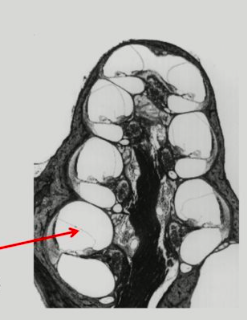

Notice the basillar artery thrombosis

Right: Cant really see the sulci (occluded by blood) and the ventricles has red cells